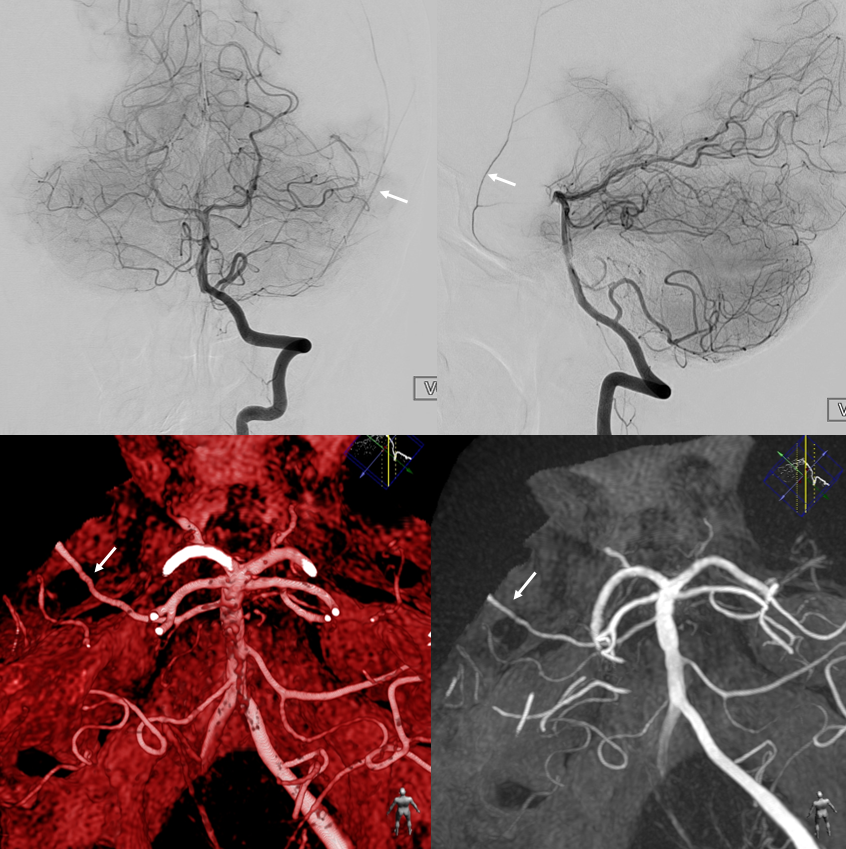

In this variant, the trigeminal artery (white arrow), supplies the lateral cerebellar territory classically belonging to the AICA In the Saltzman classification, this corresponds to Type IIIB

AP view of carotid injections showing the AICA (black arrow), with corresponding wedge-shaped void of its territory seen on the right vert injection. Notice fetal disposition of both PCOMs.

This variant can also be appreciated by an astute neuroradiologist on a CT angiogram